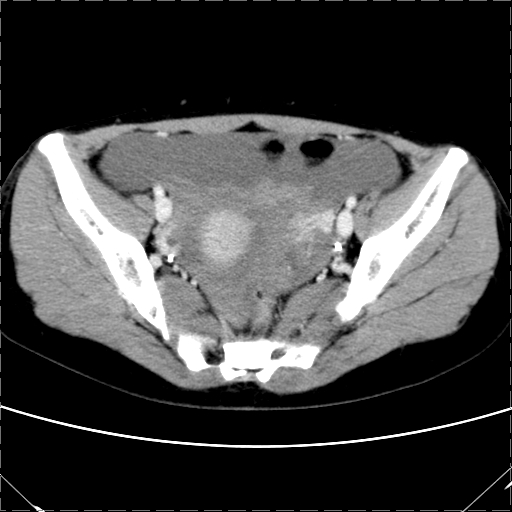

女 29岁 突然腹部疼痛1天 b超示子宫左后方肿块。月经正常。

影像表现复杂,膀胱上见一囊性包块,比膀胱密度高,其内有不均匀稍高密度,似与道格拉斯窝肿物无分界,病灶没有张力,因其腹平坦,推定其具有流动性,但又似见包膜,而b超没有报告这一现象。确实没见过。考虑卵巢囊肿蒂扭转并囊内出血可能。

病变主要位于道格拉斯窝,而且大体形态比较扁平且贴合子宫直肠,无明显张力及对周围脏器压迫,所以考虑为液体,而中间可见囊样病变伴环形强化,期内还可见分隔影,结合突发急性腹痛故多考虑囊腺瘤伴破裂出血。

腹腔镜术后 卵巢黄体囊肿破裂出血